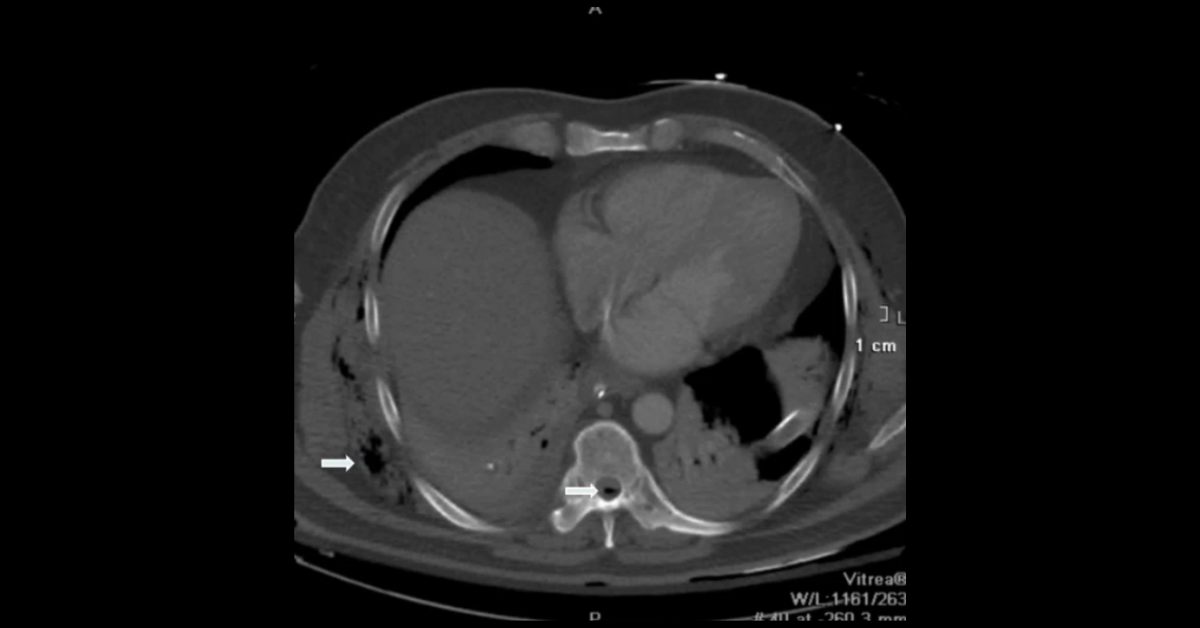

A complex case of trauma in ankylosing spondylitis highlighting complications of endotracheal tube and chest tube placement as well as focusing on the diagnosis and management of ankylosing spondylitis patients.

1. Learn the various types of chest tube misplacement.

2. Learn the complications of endotracheal intubation in ankylosing spondylitis patients.